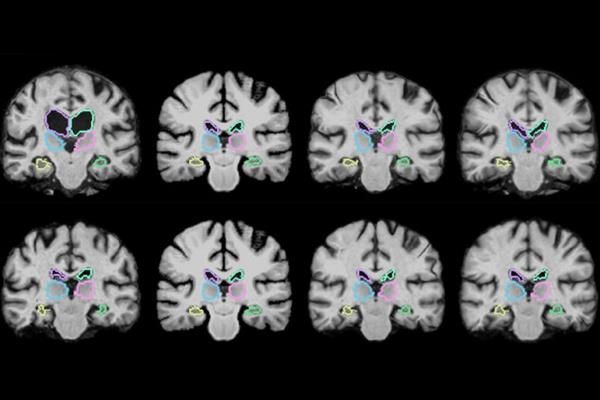

Исследователи из Массачусетского технологического института создали алгоритм машинного обучения VoxelMorph, который анализирует трехмерные изображения в 1000 раз быстрее. Алгоритм обучается, сравнивая тысячи пар снимков и подбирая идеальное расположение каждого изображения. Таким образом, система определяет универсальные оптимальные параметры калибровки – с их помощью алгоритм одновременно анализирует все пиксели в течение пары минут на обычном компьютере (или менее чем за секунду – на устройстве с мощной видеокартой).

Снимки МРТ – это сотни двухмерных изображений, собранных в 3D-модель, именно поэтому сравнение двух снимков становится чрезвычайно долгим процессом, а текущие алгоритмы начинают каждый анализ с нуля. В свою очередь, машинное обучение делает выводы из каждого сравнения, совершенствуясь и ускоряя работу. В основе VoxelMorph лежит нейросеть, которая обработала 7000 изображений МРТ мозга, опубликованных в открытом доступе.

После этого команда испытала систему, представив ей парами 250 снимков. При получении нового изображения компьютер применяет математический алгоритм для оптимального размещения вокселей и пикселей. Ученые обнаружили, что система сумела быстро и точно проанализировать все представленные снимки.

Важно отметить, что алгоритму VoxelMorph для работы не требуется дополнительной информации, помимо самих изображений МРТ. В ходе испытаний для 17 участков мозга новая система оказалась такой же эффективной, как и традиционные инструменты анализа, но при этом во много раз быстрее.